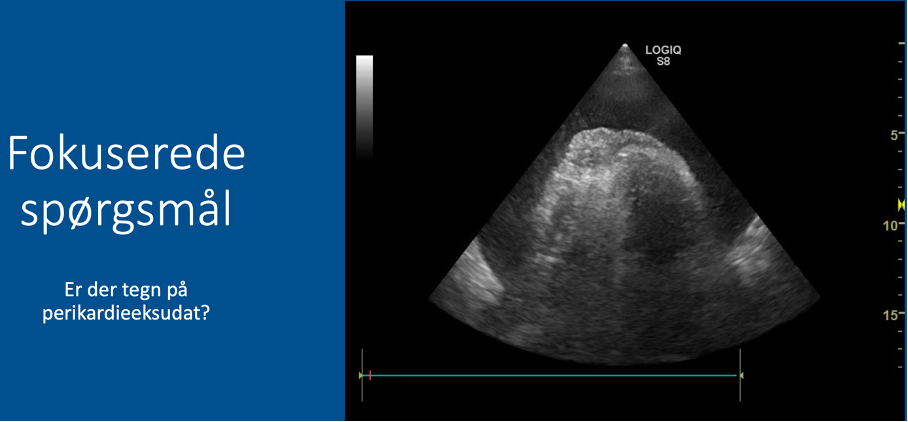

Fokuserede spørgsmål (FHUS):

* Perikardieeffusion: ja/nej?

A